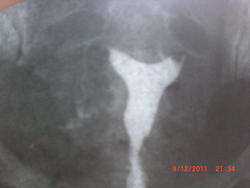

помотрите пожалуйста на мои снимки и скажите, проходимы ли трубы и есть ли гидросальпинкс.

Форма матки обычная. А вот проходимость обеих труб нарушена, вернее они не проходимы. Контраст не поступает в полость малого таза. Скорее всего какой-нибудь спаечный процесс проксимальных участках.

Вот, что пишется про интересующий объект в рентгенанатомии Коваль. Так что, гидросальпингс можно поставить под вопросом. И проходимость тоже. Свободный контраст в брюшной полости выглядит в виде перистых облаков. А тут слева - нет вообще, справа - какие-то межспаечные каналы.

Справа труба проходима. слева - нет. + признаки спаечного процесса в малом тазу.

Полностью согласен с Игорем Ивановичем. Проксимальный отдел труб расширен (в норме такое присутствует), но выхода контраста в полость малого таза нет. Насчёт гидросальпингса ничего не скажу, тут больше надо опираться на заключение УЗИ.

1.Согласен с проходимостью правой маточной трубы; слева - проходимости нет. Согласен и с фактом спаечной деформации справа.

3.Почему бы изменения трубы слева и не считать гидросальпинксом.

Вы писали: "Почему бы изменения трубы слева и не считать гидросальпинксом." ИМХО: гидросальпинкс, всё-таки когда труба расширена, а данном случае отсутствие её проходимости.

"Согласен и с фактом спаечной деформации справа." Деформации чего? маточной трубы ? , но мы же не видим деформацию самой трубы. Мне кажется, что будет точнее, если говорить  о спаечном процессе в области малого таза.